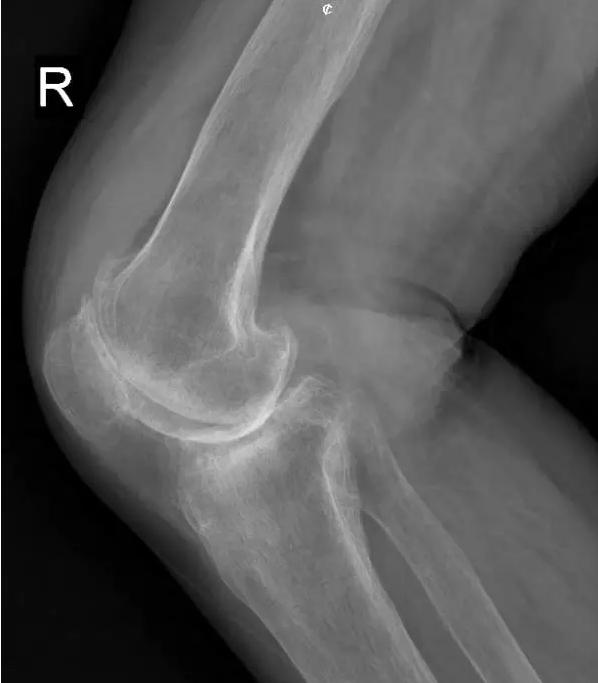

中期:骨关节炎表现为膝关节持续性疼痛,活动后或上下楼梯时加重,压痛明显; X线片上可见增生的骨赘,关节间隙出现狭窄,多为不对称性狭窄。

晚期:骨关节炎表现为膝关节明显疼痛,休息后常无缓解,伴有活动受限,可并发畸形,X 线片可见关节周围有明显的骨赘形成,或可见游离体,关节间隙明显狭窄,甚至消失。

膝关节关节镜微创治疗图(上图)

膝关节不均匀沉降术后患者X线片(下图)